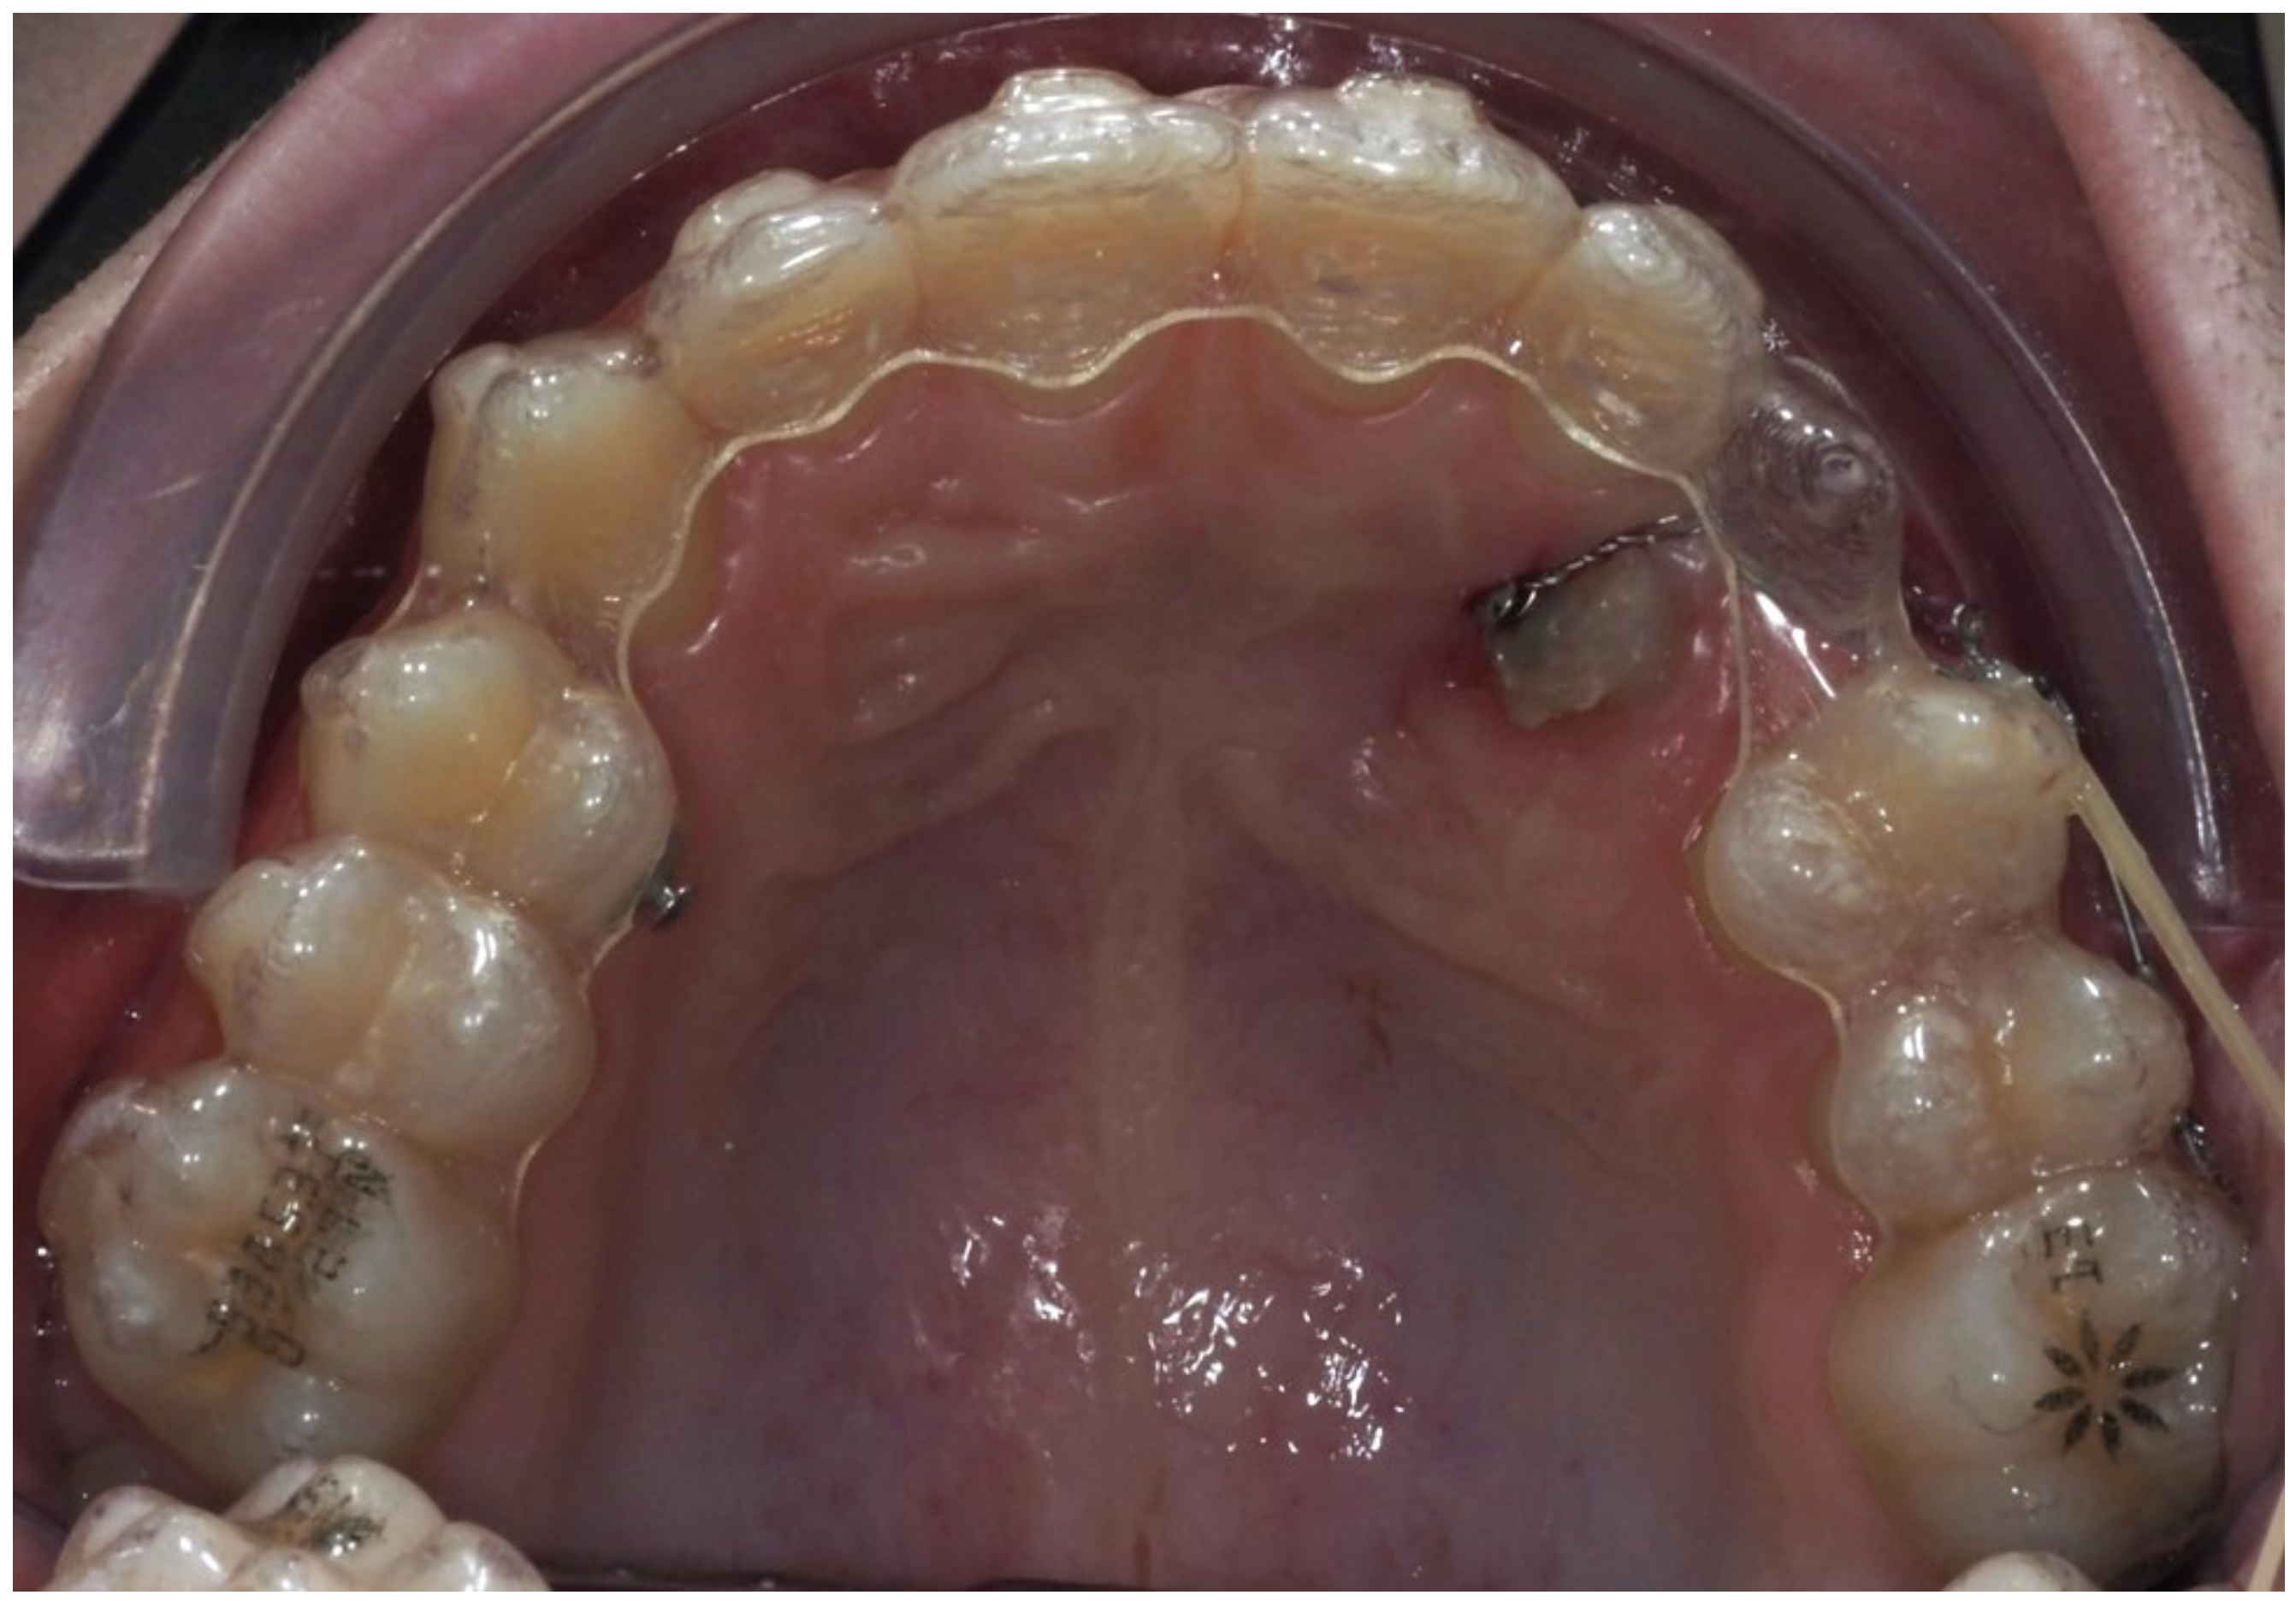

As traction progressed, the sectional appliance was extended to tooth 21 (Figure 19). A palatal button was bonded on tooth 23 to facilitate cross elastic application for vestibular movement (Figure 20). At 20 months, the bracket on tooth 23 was progressively repositioned more cervically and mesially to aid extrusion and derotation (Figure 21). A button was bonded on tooth 22 to support a wire for additional vertical anchorage. Cross elastics were also used between the palatal side of tooth 23 and buttons on teeth 33 and 34, while another elastic connected tooth 22 to 33 (Figure 22).

Figure 19.

Extension of the sectional fixed appliance up to tooth 21, with an additional tube placed on this tooth; 18 months of treatment.

Figure 20.

Palatal button on tooth 23 for cross elastic to assist in its vestibularization; 18 months of treatment.